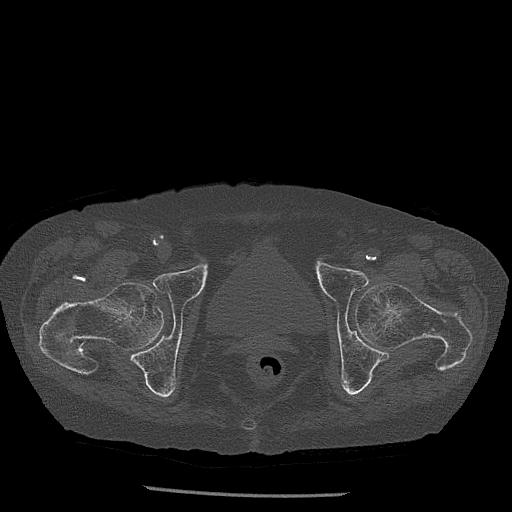

100703 1/27 両股正面+軸 1/29 両股正面+軸 94歳女性 パンソンロン

46666 1/28 両股正面+軸と 1/26 右手関節 2R 76歳女性 右転子部骨折

37 1/18 両股正面+軸 1/22 2R 86歳女性 右転子下

91569 3/25 両股正面とラウエン 70歳女性 人工骨頭+バンクーバー